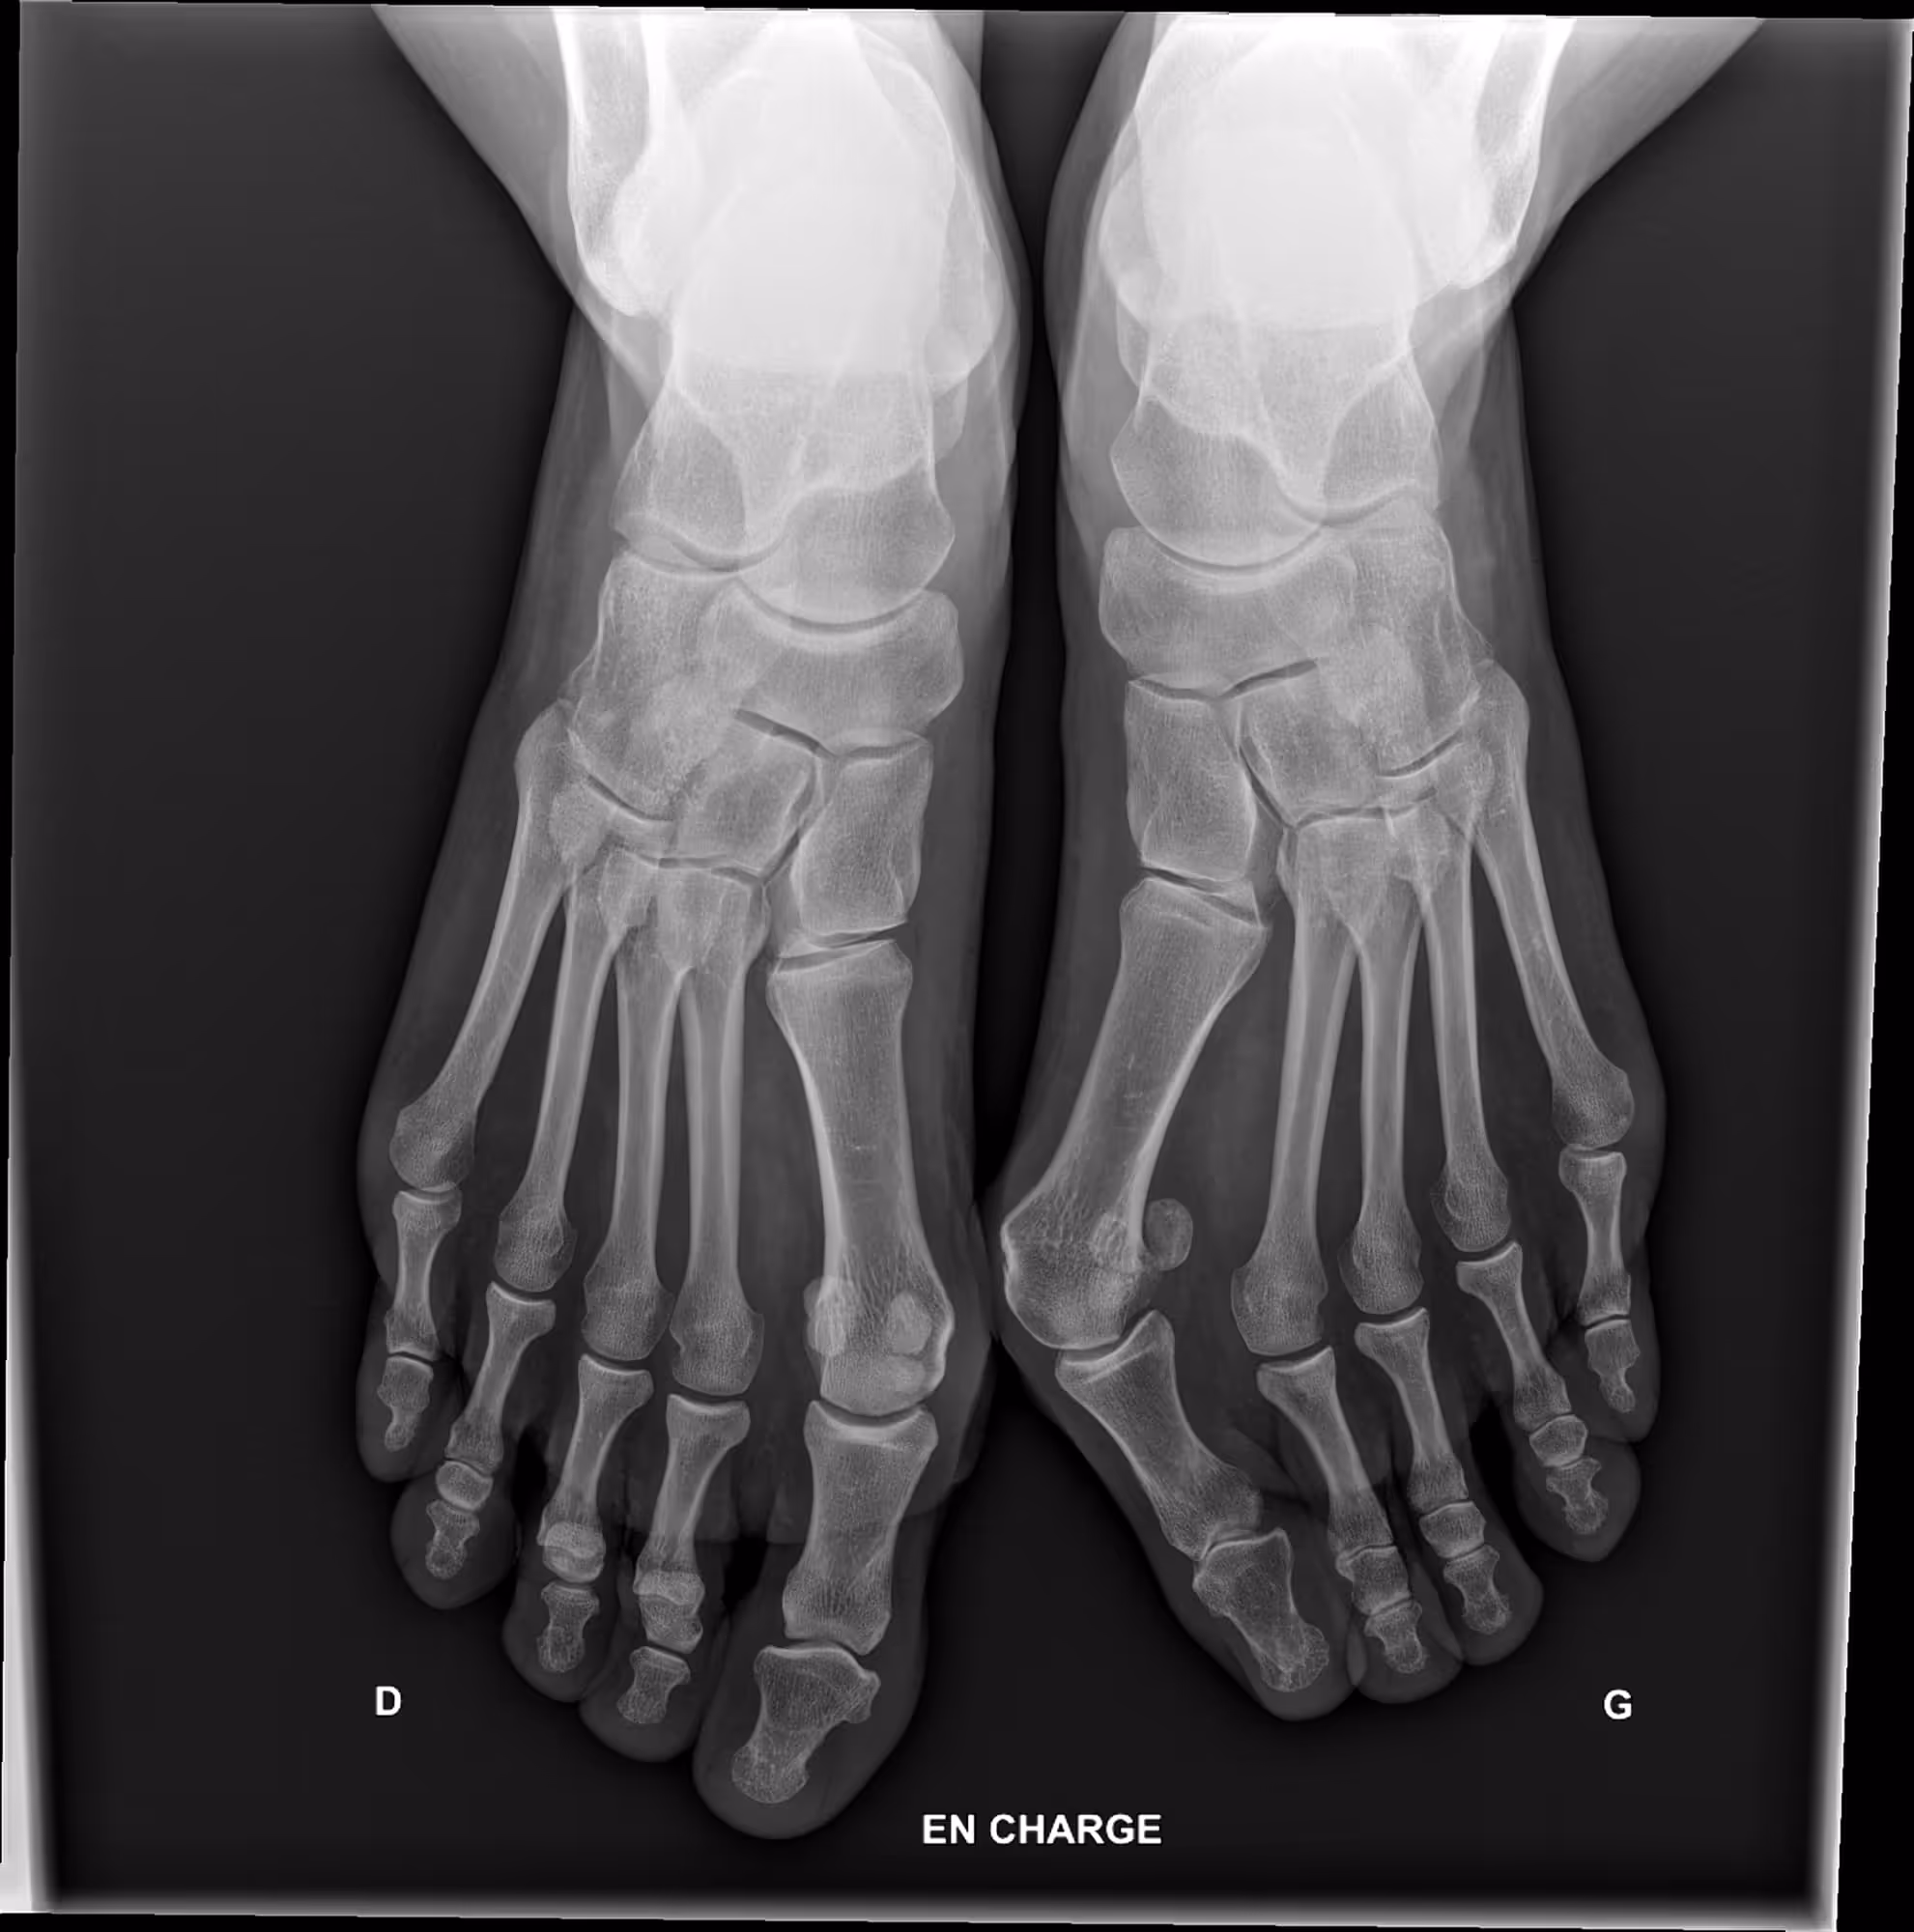

Indication

This is the defA 45-year-old female presenting with foot discomfort and difficulty wearing shoes.ault title value

Results

BoneMetrics detected a bilateral hallux valgus, with greater deformity on the left side.